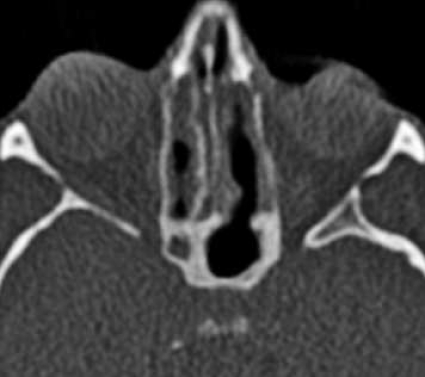

Initiala fantomstudier och pilotundersökningar visade, som förväntat, att bildkvaliteten med lågdosprotokollet blev sämre än med standardprotokollet, men den bedömdes ändå som fullt tillräcklig för den diagnostiska uppgift som avses med en konventionell röntgenundersökning av bihålorna (Figur1). Det diagnostiska värdet av lågdos-DT bedömdes av både radiologer och örondoktorer som klart överlägset värdet av en vanlig röntgenundersökning, och dosberäkningar visade också att stråldosen var lägre för lågdos-DT än för konventionell röntgenundersökning.

Resultaten visar klart att lågdos-DT ger bra visualisering av samtliga näsans bihålor, och man kunde med lätthet både påvisa och utesluta engagemang av såväl frontalsinus som sfenoidalsinus och inte minst av etmoidalsinus, ett område där den konventionella teknikens tillkortakommanden är väl kända. Lågdos-DT visade sig också möjliggöra en diagnostisk bedömning av anatomiska nyckelstrukturer såsom infundibulum och frontonasala recessen.

Användandet av lågdos-DT innebär sålunda inte bara en säkrare diagnostik av bihåleförändringar än med vanlig röntgenundersökning, utan man får också viktig tilläggsinformation, som inte kan erhållas med vanlig röntgenundersökning. Även möjligheten att visualisera små, men kliniskt relevanta anatomiska avvikelser (tex concha bullosa, Haller-celler och dysplasier), postoperativa förändringar, benförändringar vid kronisk sinuit och odontogena orsaker till sinuit, gör lågdos-DT klart överlägsen konventionell röntgenundersökning vid sinuit (Figur2).